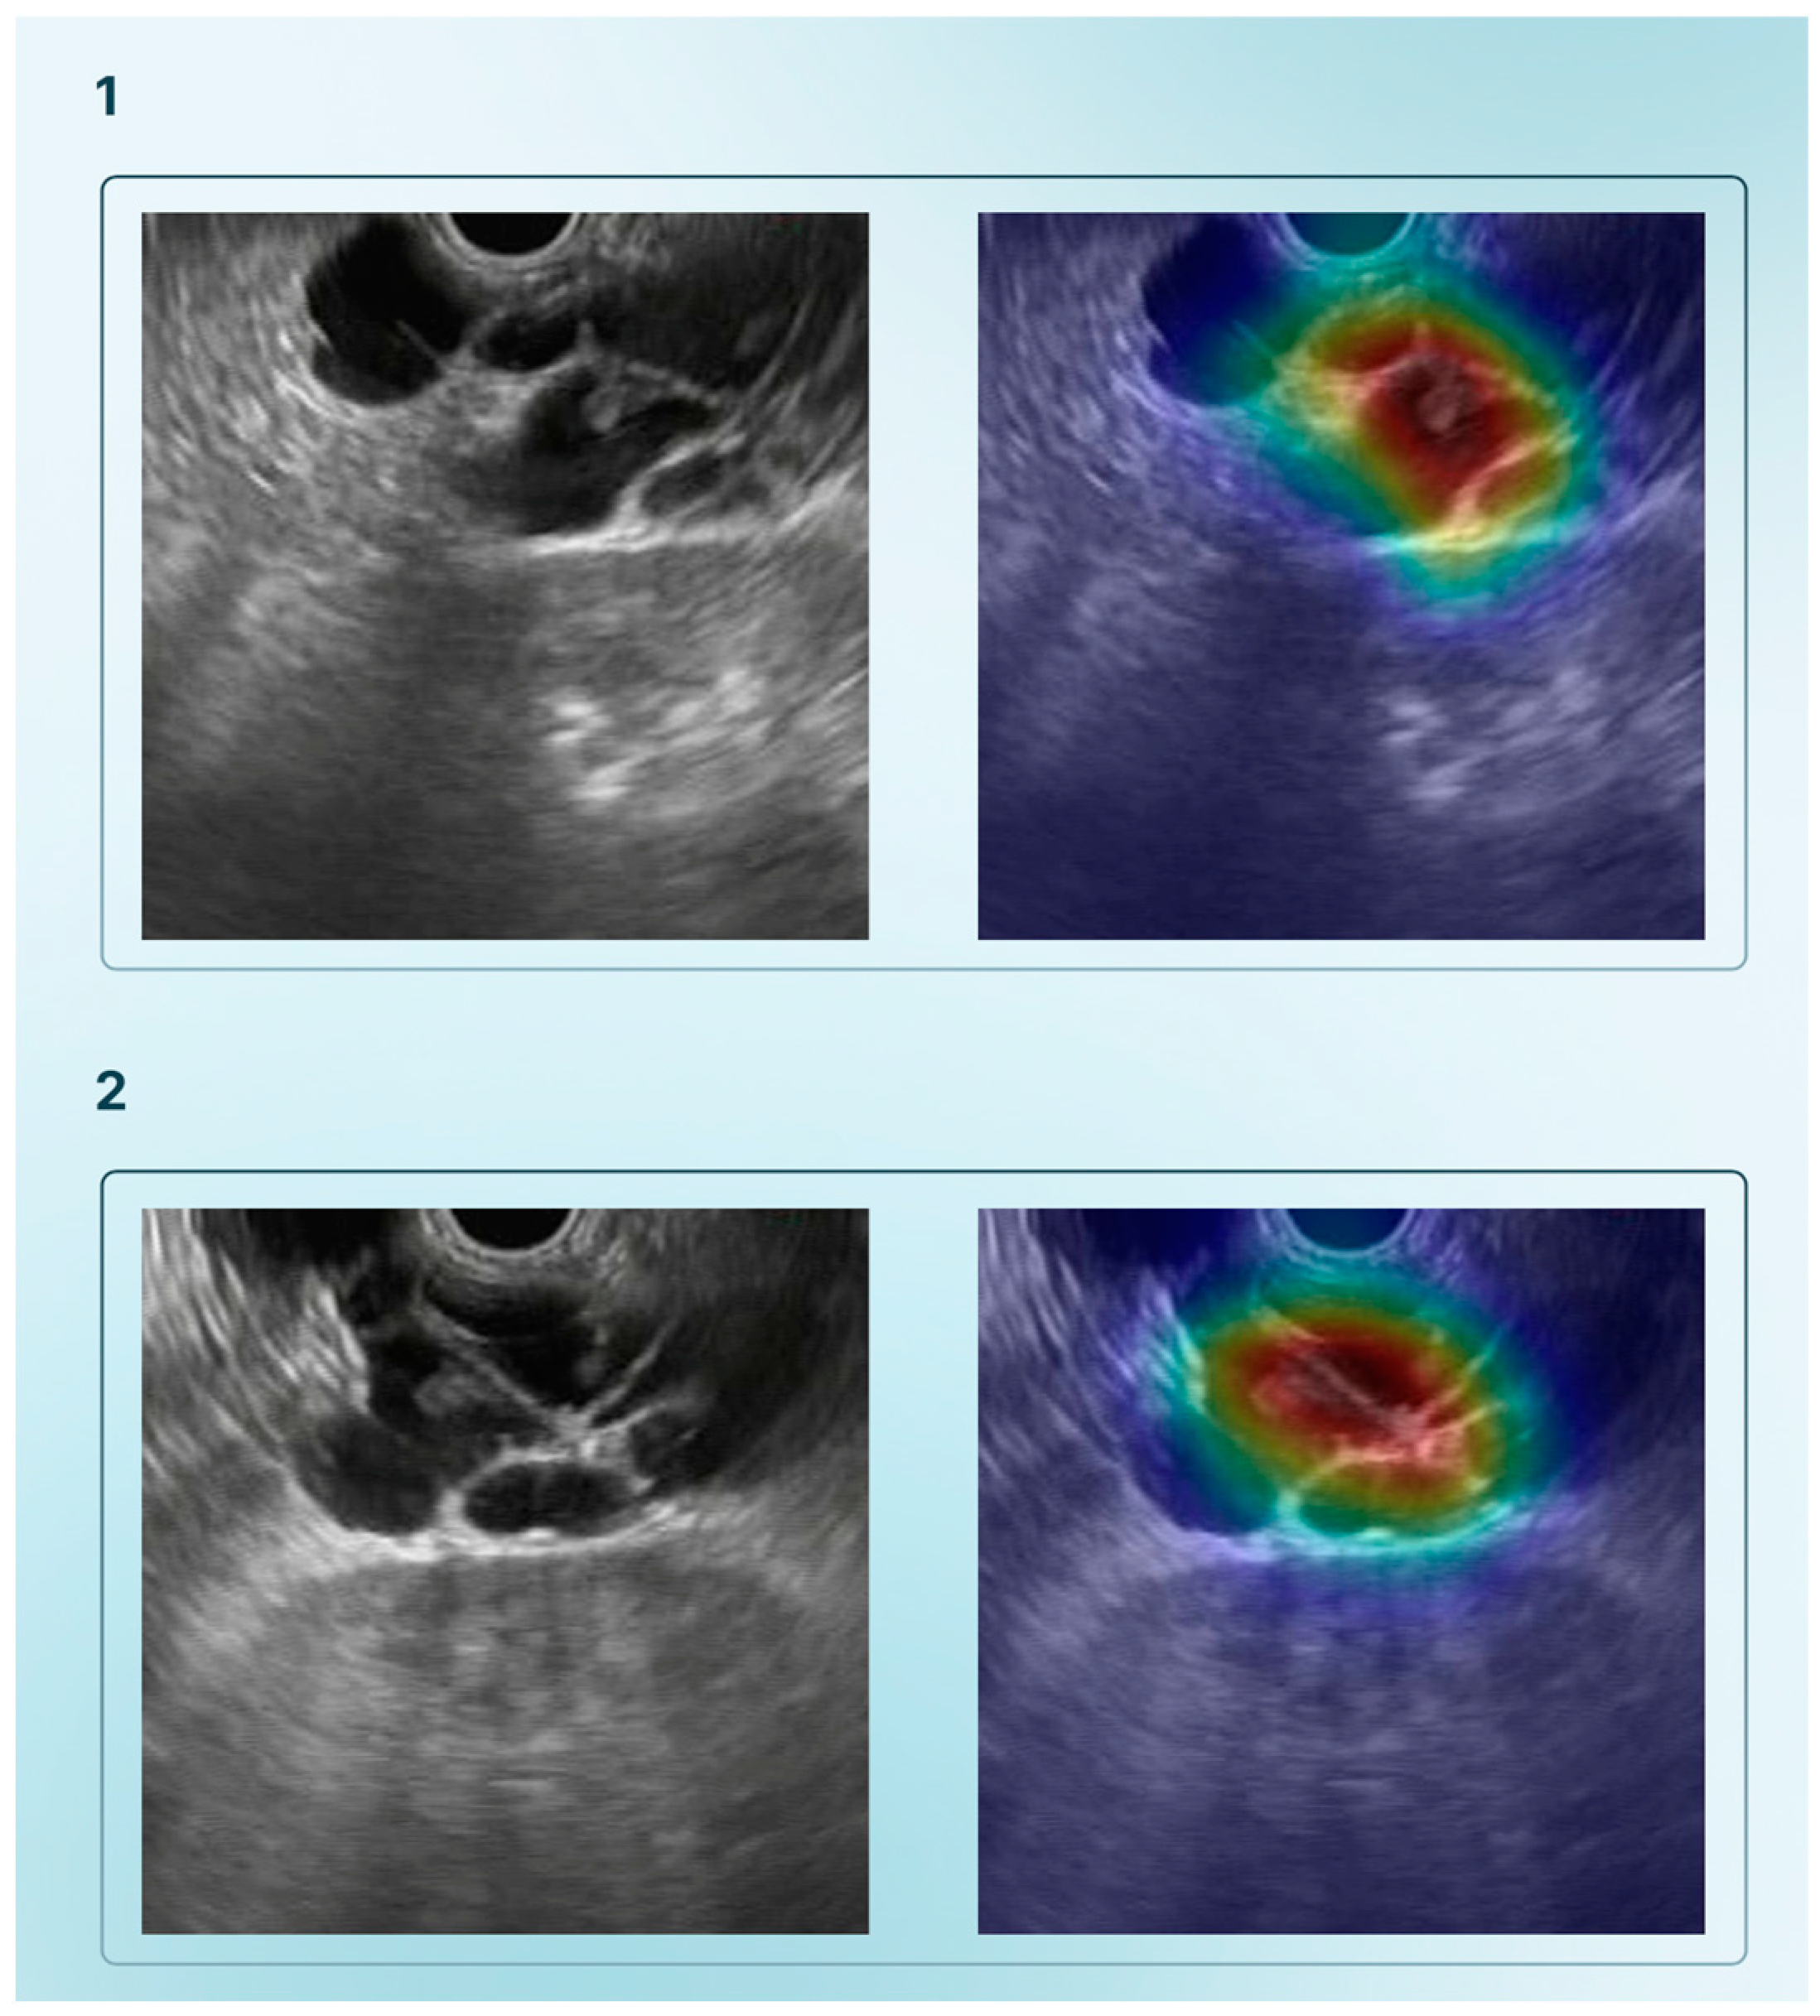

| Tonozuka et al., 2021 [27] | Detect PDAC from EUS images using a DL model | 1 | NK | 1390 static images (with data augmetation 88,320) | NK | CNN and pseudocolored heatmap | Frame labelling of all datasets (PDAC, CP, or NP) | Train–validation–test (training–validation set ratio: 90–10%; 10-fold cross–validation) | PDAC, CP, NP | 92.4% | 84.1% | 0.940 |